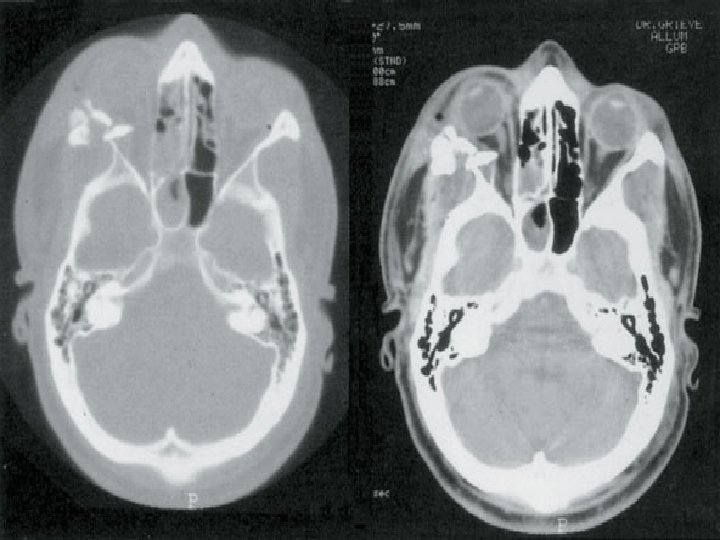

FRACTURAS DE LA ORBITA: � Fractura por explosion (BLOW-OUT) del piso de la orbita; � Fractura por explosion (BLOW-OUT) de la pared medial; � Fractura del teto; � Fractura de la pared lateral;

Fractura por explosion (BLOWOUT) del piso de la orbita; fractura blow-out implica el borde y los huesos faciales adyacentes. La fractura blow-out del piso orbitario tipicamente es causado por um subito aumento de la presion orbitaria por impacto de um objeto superior a 5 cm de diametro, tal como un puño o pelota de tenis. � Las fracturas mas frecuentes involucran el piso orbitario al longo de los huesos finos que forman el canal infraorbitario. � Ocasionalmente, la pared medial de la orbita tambien puede ser fracturada. � La

Fractura por explosion (BLOWOUT) de la pared medial � Muchas fracturas de la pared medial son frecuentemente asociadas a las fracturas del piso orbitario. � Las fracturas de la pared medial son menos comunes.